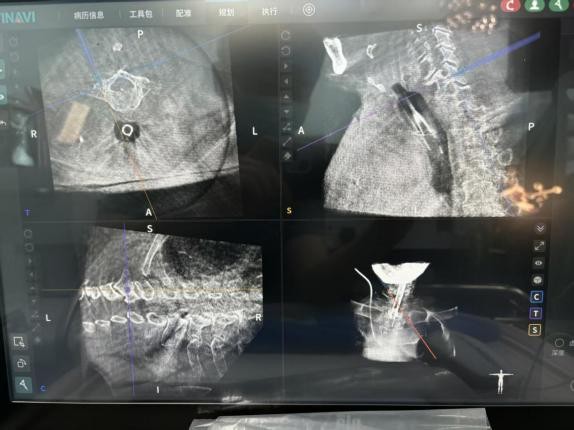

凭借机器人的亚毫米级的稳定性和三维空间精准定位能力,完美突破了传统手术的局限。术前,机器人为每一枚椎弓根螺钉的置入规划最优路径,打造精准手术「蓝图」;术中,实时导航辅助操作,全程监测、调整螺钉置入方向,从矢状位、冠状位、轴位多维度把控置钉角度,有效规避了神经、血管损伤的风险,大幅降低了手术潜在风险。同时,机器人还能实现术中即刻扫描,螺钉位置清晰可见,彻底解决了传统透视的遮挡难题。